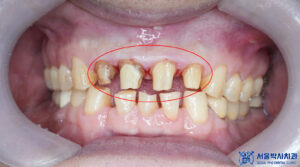

제거를 하고 확인해 보니,

내부로 충치가 생긴 것을

확인할 수 있었습니다.

이로 인해 불편감을

느끼고 계셨을 것으로

예상하였습니다.

본원에서는 충치가 있는 부분을

깨끗하게 제거하고,

신경치료를 진행하여

자연치아를 살리는 방향으로

계획을 수립하였습니다.

충치를 제거하고

신경치료를 시작하였습니다.